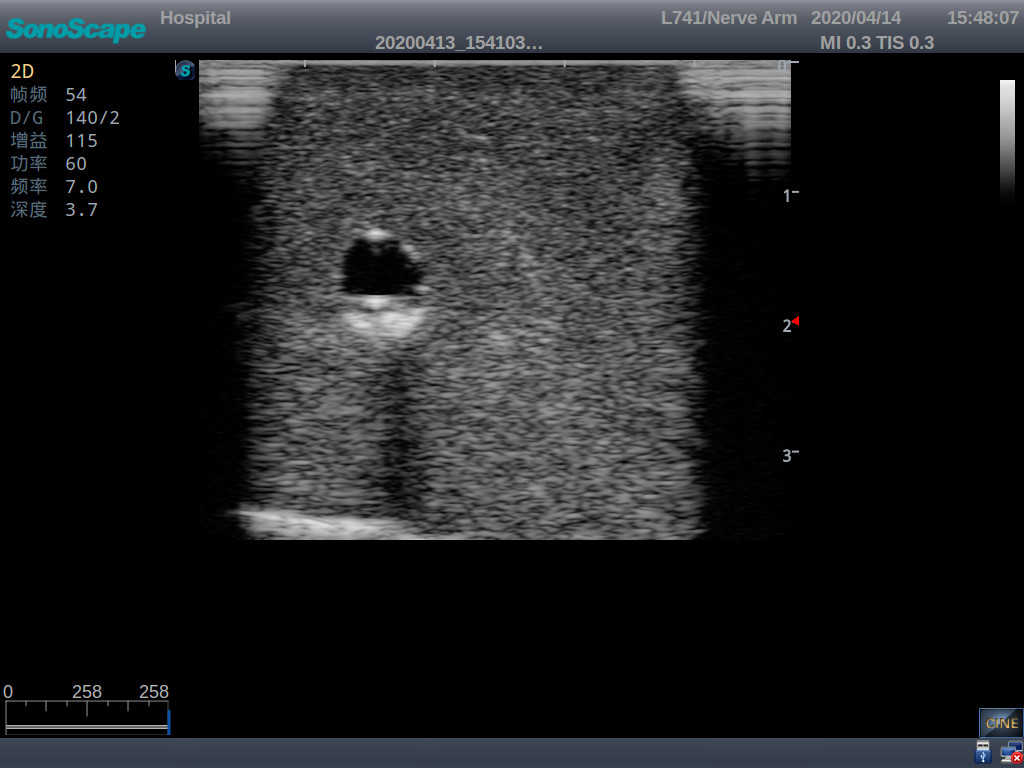

PICC Ultrasound Training Model

Model TYE1510.1

It is a model covering up from lobulus auriculae plane to the umbilical plane, and it has anatomical structures like clavicle, rib, sternocleidomastoid, jugular vein and basilic vein.

1)   Made of high molecular polymer ultrasound material, close to the real skin

2)   It can be used by real ultrasound machines

3)   Clear and real images of the tissues and organs (basilic vein and superior vena cava)

4)   When conducting vascular puncture, the piercing can be truly felt, and venous blood outflow can be seen

5)   Observe the guide wire marches

6)   Detect whether the catheter is properly placed